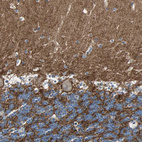

Immunohistochemistry analysis in human cerebral cortex and pancreas tissues using HPA008832 antibody. Corresponding NFASC RNA-seq data are presented for the same tissues.